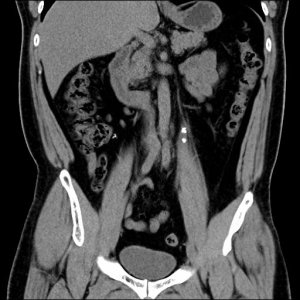

After surgery, there was another KUB done to confirm the location of the stent. The stent protects the ureter from any leftover debris of the pulverised stones.

The X-ray report confirmed that the stent was in the right place. I was out of the OT by 3 pm. At 6pm, the surgeon allowed me to remove the CBD (continuous bladder drainage). I was no longer bed-ridden therefore I was a happy man, and I immediately went down to surau to pray asar and qada’ zohor. Sadly the shops were closed already by then, so I couldn’t buy anything to eat. After 24 hours of observation, I was discharged on Friday morning.